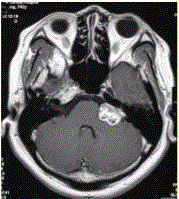

问题 患者女,40岁。左侧听力下降半年,临床治疗效果不显著。MRI增强检查如下图。 可能的诊断是

选项 A.神经鞘瘤 B.脑膜瘤 C.表皮样囊肿 D.蛛网膜囊肿 E.星形细胞瘤

答案 A